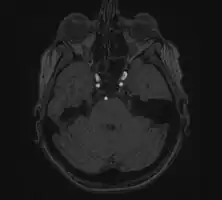

Endovascular coiling

Endovascular coiling refers to the insertion of platinum coils into the aneurysm. A catheter is inserted into a blood vessel, typically the femoral artery, and passed through blood vessels into the cerebral circulation and the aneurysm. Coils are pushed into the aneurysm, or released into the blood stream ahead of the aneurysm. Upon depositing within the aneurysm, the coils expand and initiate a thrombotic reaction within the aneurysm. If successful, this prevents further bleeding from the aneurysm.[33] In the case of broad-based aneurysms, a stent may be passed first into the parent artery to serve as a scaffold for the coils.[34]